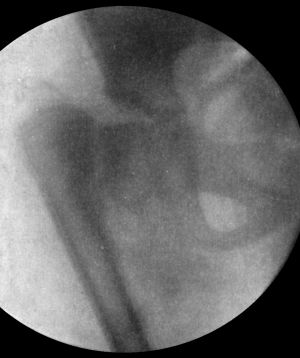

103.Arthropathy of Shoulder in Syringomyelia203

104.Radiogram of Specimen of Arthropathy of Shoulder in Syringomyelia204